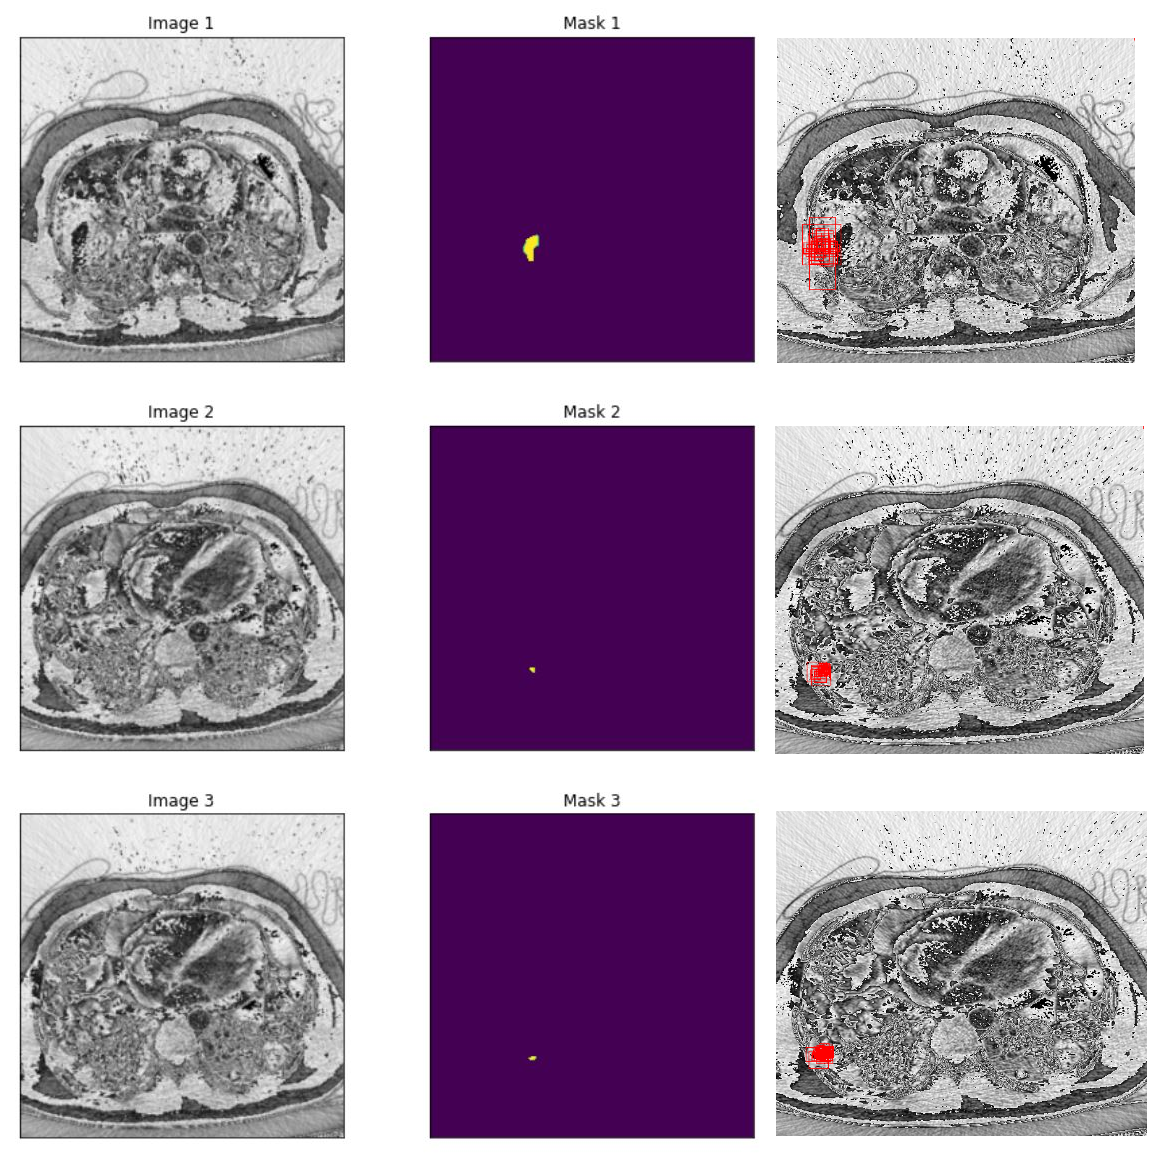

Localization results

Figure 10: PE Localization predictions using PE pretrained ResNet50.

Slice Level Image Localization

In our research, we employed two pre-trained models, ResNet-50 and Swin Transformer Tiny, for the classification task in PE detection. The ResNet-50 model delivered impressive results with a testing accuracy of 0.92 and an AUC score of 0.98. The Swin Transformer Tiny model demonstrated a satisfactory performance with a prediction accuracy of 0.87 and an AUC score of 0.97. Subsequently, we leveraged the pre-trained classification model to train our segmentation branch using the U-Net architecture. This strategy significantly improved the segmentation performance, as observed in the substantial increase in IoU scores when using pre-trained weights from the PE dataset. The scores reached 0.88 and 0.82 for the ResNet-50 and Swin Transformer Tiny models, respectively. This highlights the benefit of model integration, which improved PE detection in the segmentation task. Finally, we focused on the localization task, using the PE pre-trained ResNet-50 model as the feature extractor for the Faster R-CNN architecture. The model performed excellently in determining the approximate location of PE instances in CTPA images, with an IoU score of 0.836. Further, precision and recall metrics were calculated to assess the model’s ability to identify true positive instances accurately while minimizing false positives and negatives.